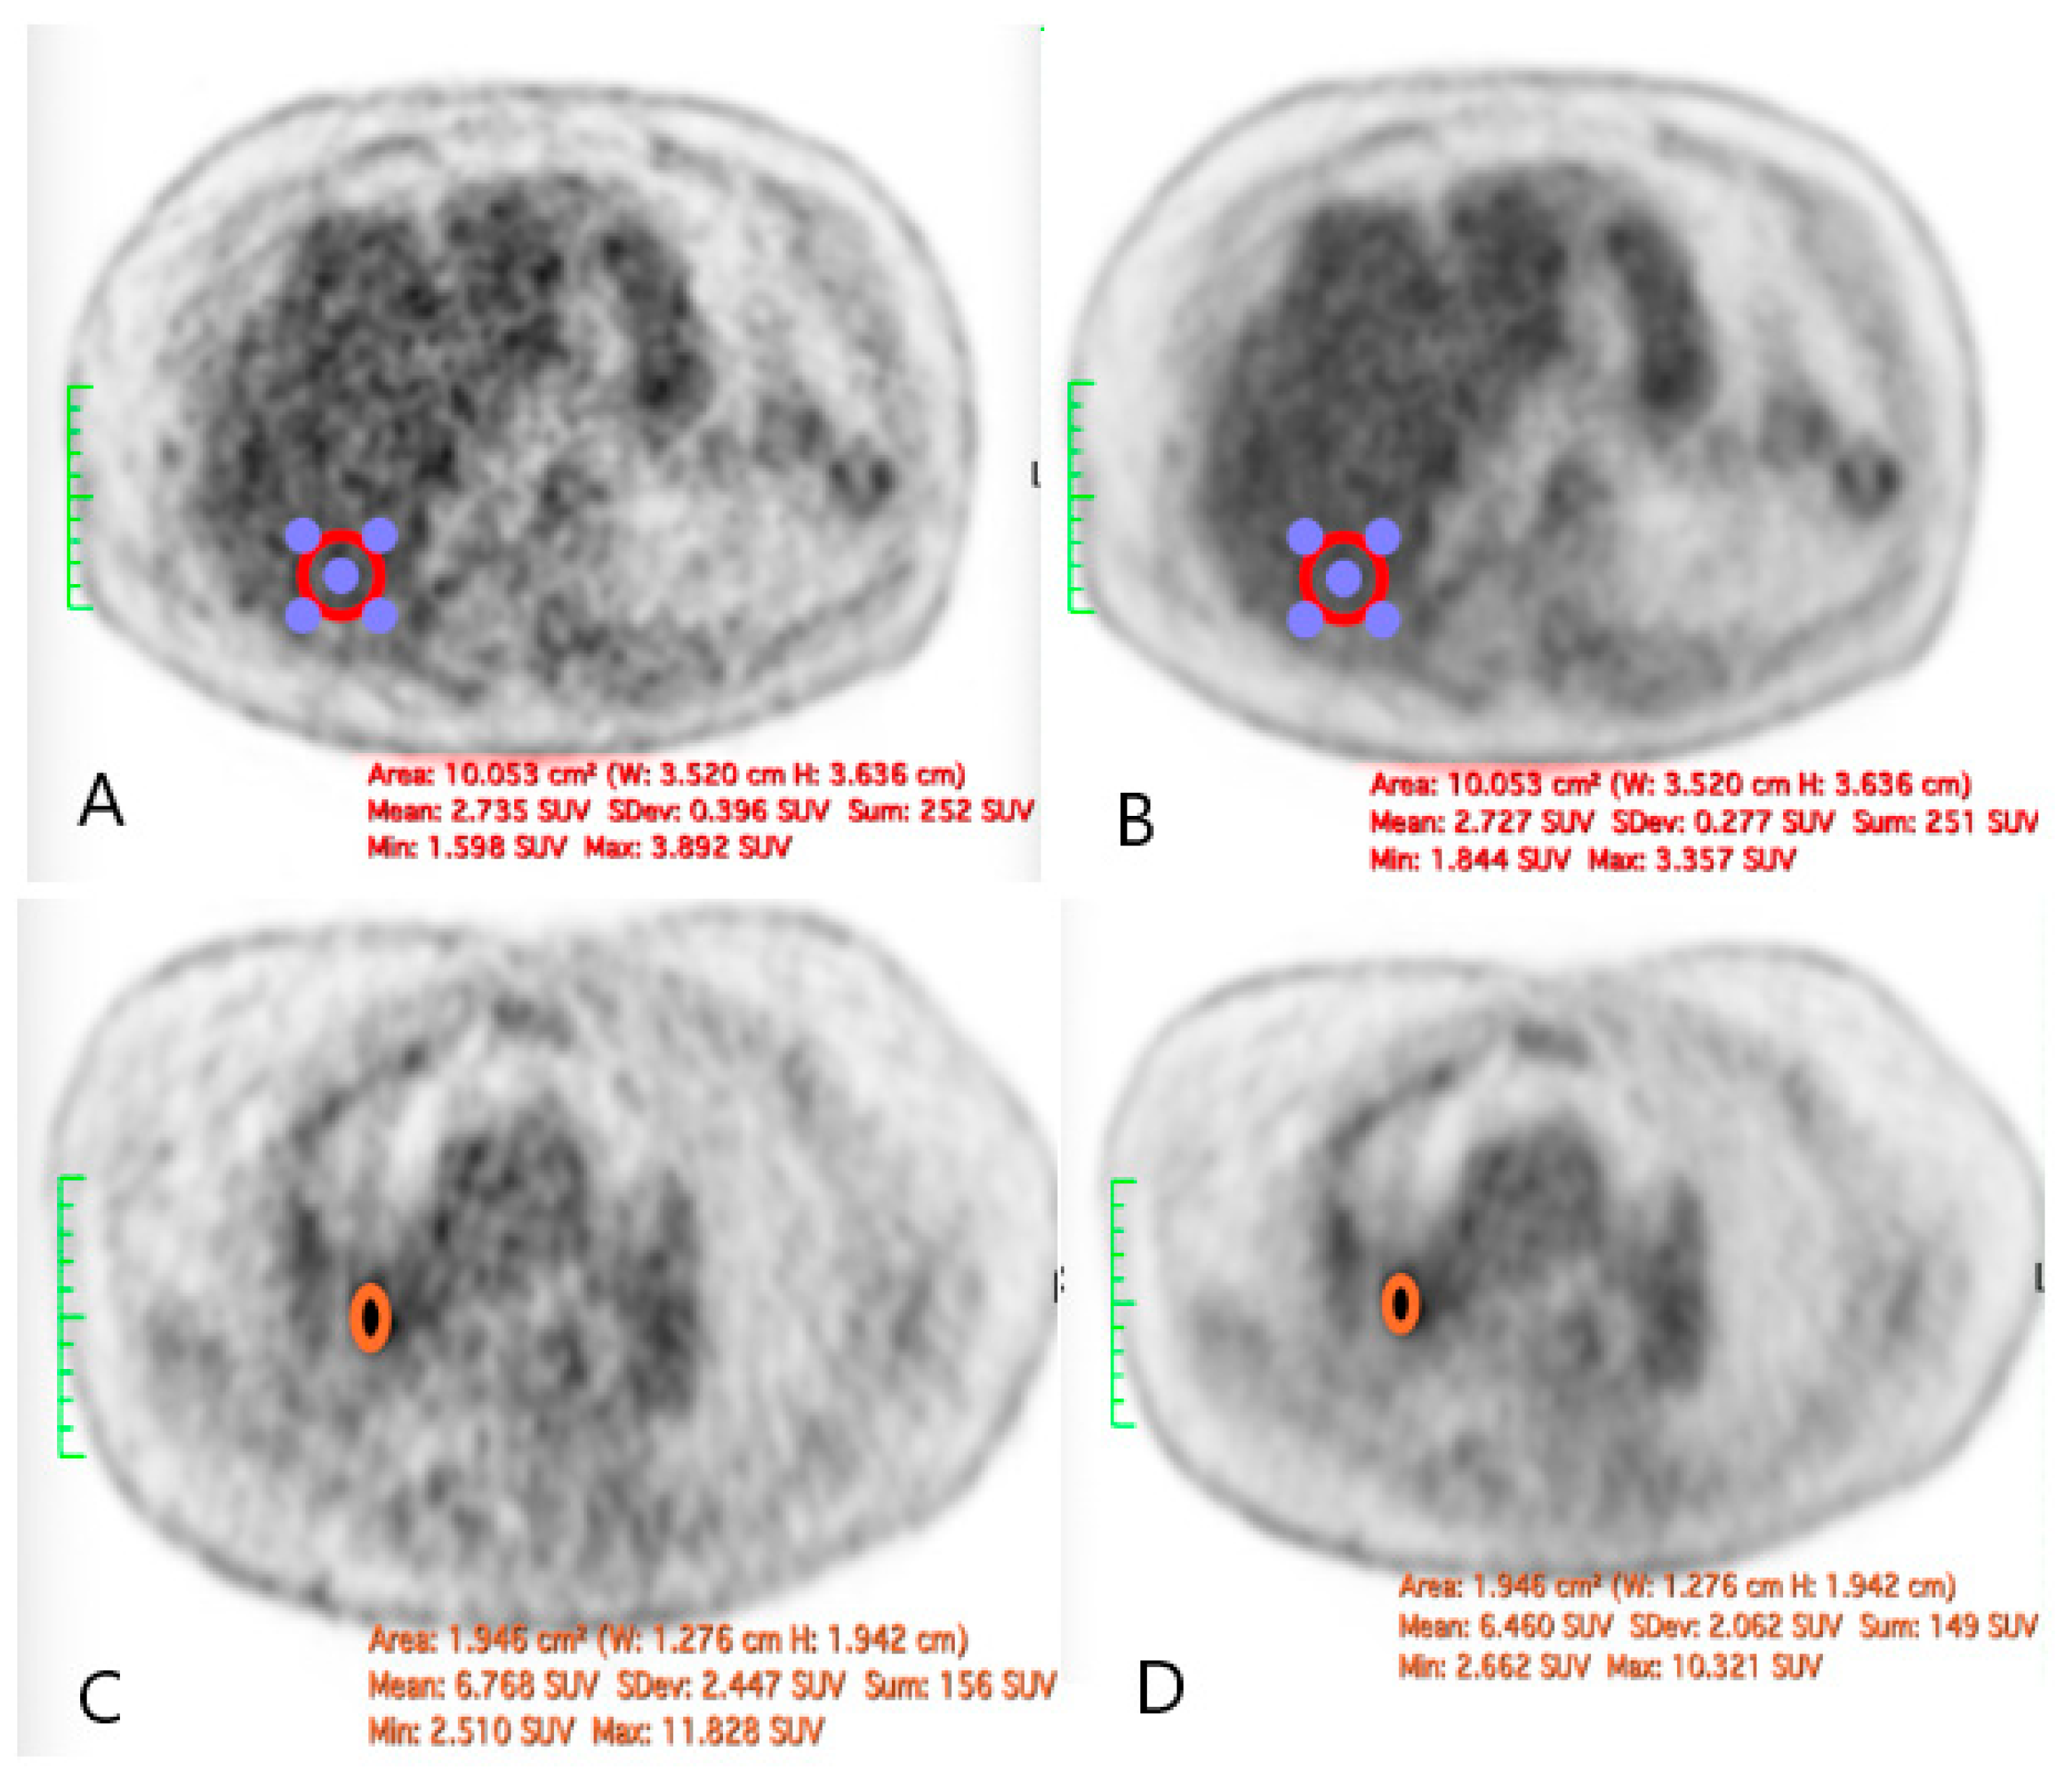

Across the three radiotracers, the AI-denoised images demonstrated a significantly improved performance in the visual analysis compared to conventional PET images. AI-denoised images were rated as interpretable (scores of 3–5) in all cases, compared to 65% for conventional images. Furthermore, an excellent image quality (score of 5) was achieved in 85% of all AI-denoised images, a significant improvement compared to the 50% in standard acquisitions. SubtlePET™ processing resulted in consistently lower noise levels, particularly for 18F-FDG scans, where 85% of images scored 4 or 5 for noise reduction compared to 60% in conventional scans. Lesion detectability was maintained or enhanced across all radiotracers, ensuring no compromise in the diagnostic accuracy. For 18F-FDOPA, a tracer with inherently lower signal-to-noise ratios, the AI algorithm improved the detection confidence by 25% compared to standard protocols. The visual comparison is illustrated through different MIP images and transaxial images (Figure 1, Figure 2, Figure 3 and Figure 4)

Figure 2. Total body 18F-FDG PET CT, MIP and transaxial images (left: without AI denoising; right: with AI denoising).